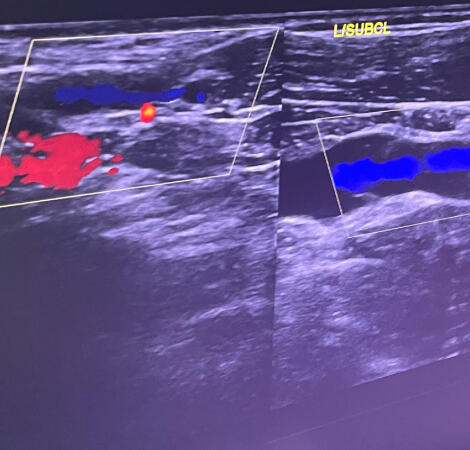

Η διάγνωση και η θεραπεία του ΣΘΕ μπορεί να περιλαμβάνει κλινική εξέταση, εικονολογικές εξετάσεις (όπως ακτινογραφίες, υπερηχογραφίες), και σε ορισμένες περιπτώσεις, ηλεκτροδιαγνωστικές εξετάσεις για την αξιολόγηση της νευρομυϊκής λειτουργίας.